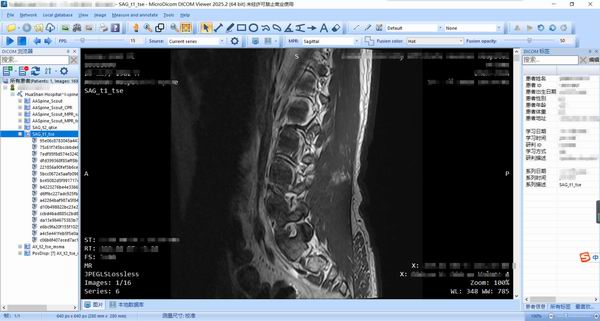

[下载]一款免费看DCM格式医疗影像的软件——MicroDicom

Honker.org.cn红盟网讯 最近去华山医院拍MR磁共振,检查出来后并没有直接打印(另收费),经中医师讲起,在检查单上有二维码,随即扫描后,发现是有图像可以自行查看的。

不过网站可能不能存放太久,为了防止数据被删除,还是希望把资料保存到本地,于是考虑从网站上下载下来,回家后,通过电脑,经过一番折腾,终于把资料下载到本地,这样就相对安心了,下次去中医那就可以给医生看了。

MicroDicom是一款专业且功能强大的医学图像浏览工具。MicroDicom官方版能够帮助医学工作者轻松的浏览各种dcm格式的医学图像,包括RLE、JPEG、JPEG2000等格式。MicroDicom软件还支持将dcm转换为常见的jpg、bmp等图像格式